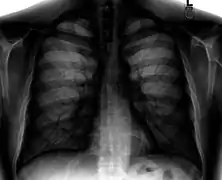

Chest film showing increased opacity in both lungs, indicative of pneumonia